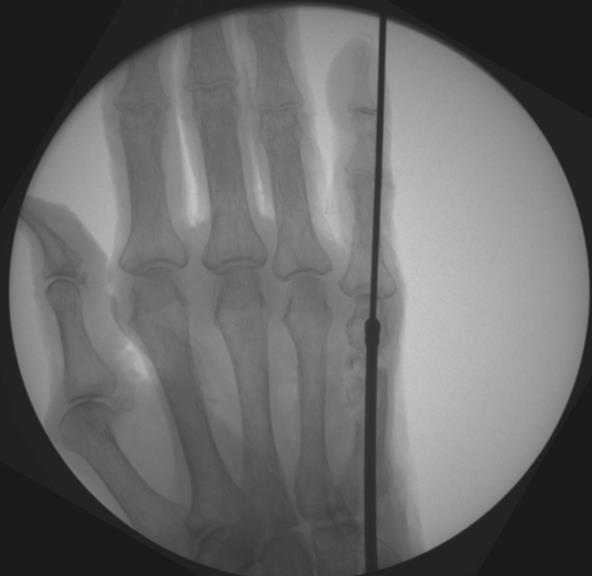

• Technique

• Metacarpal Technique

• step 1

• insert a 1.6mm k-wire into the metacarpal head and advance it to the fracture site

• reduce the fracture under fluoroscopy and advance the k-wire into the metacarpal base

• confirm fracture reduction and final nail position with fluoroscopy, ensuring the locking screw holes are not near fracture lines

• confirm final reduction and implant position using fluoroscopy